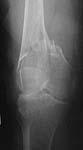

Please see attached pics of an 82 yo woman who lives independently and is a community ambulator s/p low energy fall w/ SC femur fx below a stable uncemented THA (1990).

Looks like SupraCondylar, and IntraCondylar involvements.